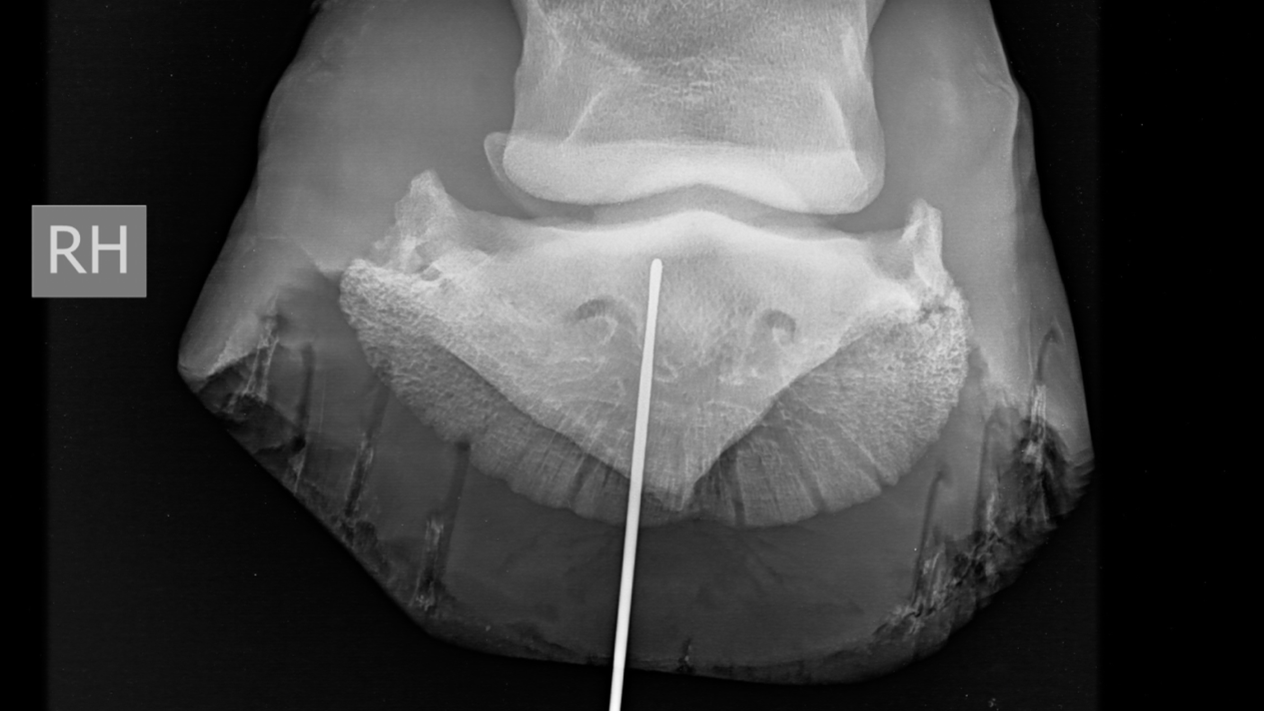

Er werden vervolgens radiografieën (LM; DPr-PlDiO) met metalen sonde genomen. Welke anatomische structuren zijn mogelijks betrokken?

DPr-PlDiO

De metalen sonde heeft een proximoplantaire richting en eindigt ter hoogte van het plantaroproximaal aspect van het hoefbeen en distaal van de distale rand van het straalbeen.

Anatomische structuren welke hoogstwaarschijnlijk betrokken zijn bij deze nageltred zijn: de diepe buigpees, lig. sesamoideum distale impar, de bursa podotrochlearis en de plantarodistale recessus van het hoefgewricht.

Geen bot afwijkingen vastgesteld.